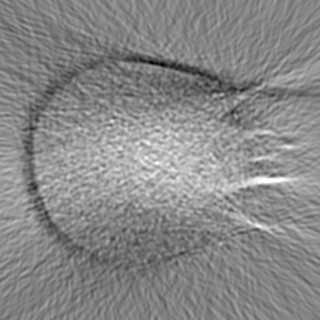

Cone-beam CT (CBCT) employs a flat-panel detector to achieve three-dimensional imaging with high spatial resolution. However, CBCT is susceptible to scatter during data acquisition, which introduces CT value bias and reduced tissue contrast in the reconstructed images, ultimately degrading diagnostic accuracy. To address this issue, we propose a deep learning-based scatter artifact correction method inspired by physical prior knowledge. Leveraging the fact that the observed point scatter probability density distribution exhibits rotational symmetry in the projection domain. The method uses Gaussian Radial Basis Functions (RBF) to model the point scatter function and embeds it into the Kolmogorov-Arnold Networks (KAN) layer, which provides efficient nonlinear mapping capabilities for learning high-dimensional scatter features. By incorporating the physical characteristics of the scattered photon distribution together with the complex function mapping capacity of KAN, the model improves its ability to accurately represent scatter. The effectiveness of the method is validated through both synthetic and real-scan experiments. Experimental results show that the model can effectively correct the scatter artifacts in the reconstructed images and is superior to the current methods in terms of quantitative metrics.